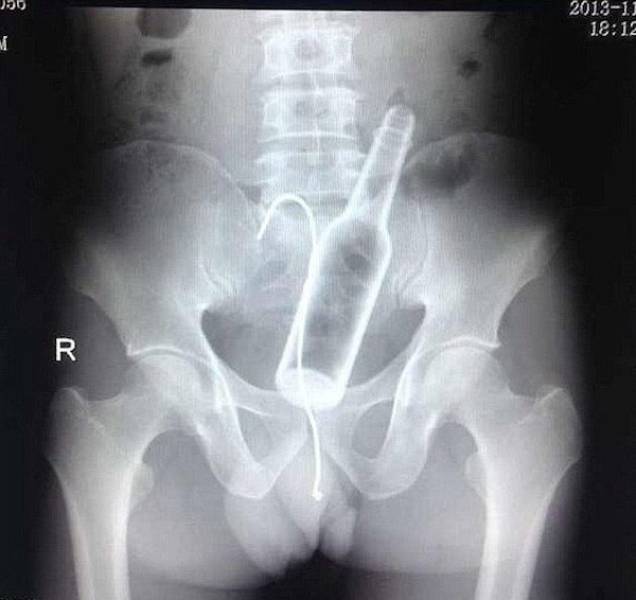

Man puts wire up his rectum to get stuck wine bottle.

Both get stuck. As ever.